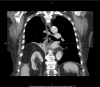

Intrathoracic kidney is a very rare finding, representing less than 5% of all renal ectopias. Because of the location of the liver, thoracic kidney on the right side is much less common than thoracic kidney on the left side. Although an increasing number of case reports are being published in the literature, few describe the impact of the ectopia on kidney function. We report the case of a woman with intrathoracic right kidney and chronic kidney disease that was initially misdiagnosed as pneumonia because of its presentation on chest x-ray. We highlight the need to including this condition in the differential diagnosis[2] as the literature rarely links it to changes in kidney function.

Learning points: Intrathoracic kidney is an extremely rare condition that should be considered in the differential diagnosis of intrathoracic masses.There is a lack of literature on this type of kidney ectopia and its consequences in asymptomatic individuals.